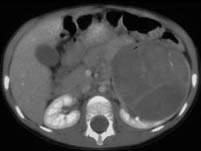

问题 女,54岁,发现腹部包块,请根据所示图像,选择最可能诊断 ( )

选项 A、左侧囊性肾癌 B、左侧肾血管平滑肌脂肪瘤 C、左侧单纯性肾囊肿 D、左侧肾囊肿合并出血 E、左侧肾癌

答案 A